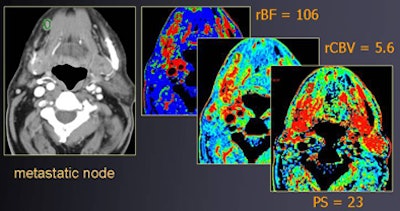

![]() |

| Round shape (contrast-enhanced CT, above) suggests suspect nodes in a patient with right-sided oral cancer. At perfusion CT (below), relative blood volume and permeability surface area product values of right lymph node are elevated compared to the contralateral side, showing hyperperfusion. Histopathology confirmed the malignancy. All images courtesy of Dr. Agneistsa Trojanowska. |